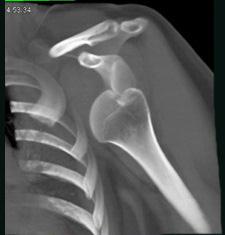

问题 男,18岁,肩部外伤,疼痛、活动受限,结合图像,最可能的诊断是 ( )

选项 A、肩锁关节脱位 B、肩关节未见脱位 C、肩关节喙突下脱位 D、肩关节锁骨下脱位 E、肩关节盂下脱位

答案 E